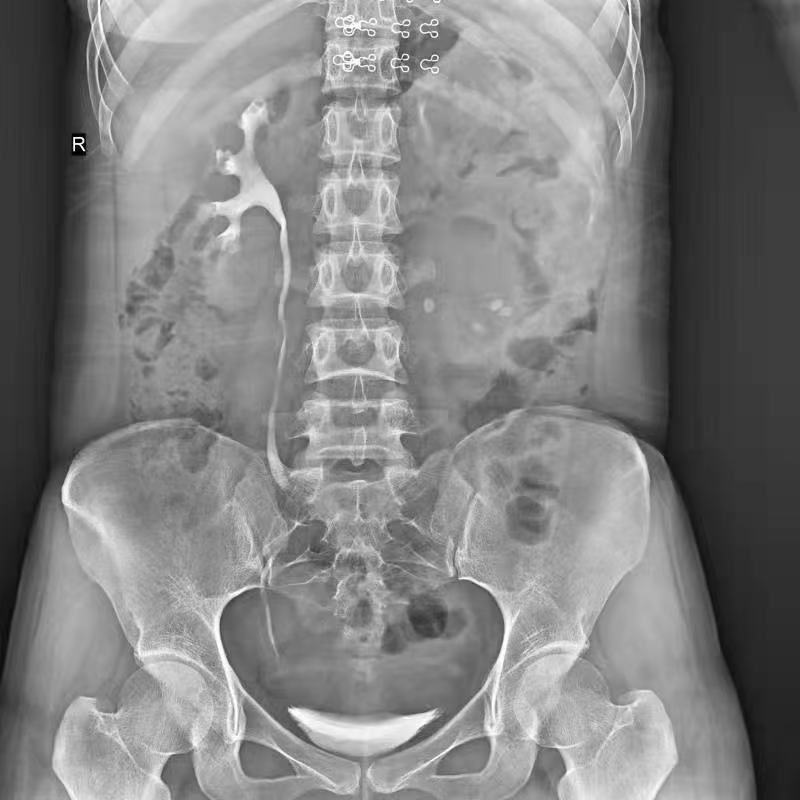

點(diǎn)片裝置移動(dòng)范圍大,無(wú)需患者移動(dòng)就能完成全身各部位的檢查;

床面橫向移動(dòng),輕松實(shí)現(xiàn)機(jī)動(dòng)人不動(dòng)。